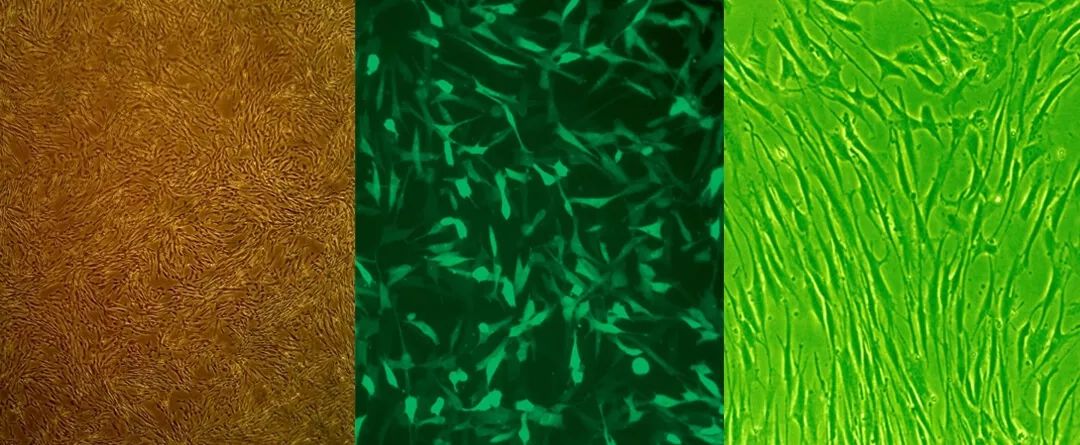

LONZA原代血管平滑肌细胞,由健康人或病人捐赠,其包括多种组织来源的细胞,如主动脉平滑肌细胞(Human Aortic Smooth Muscle Cells,简称AoSMC)、肺动脉平滑肌细胞(Human Pulmonary Artery Smooth Muscle Cells)、冠状动脉平滑肌细胞(HumanCoronary Artery Smooth Muscle Cells)等。LONZA可提供不同人种、性别、年龄单个供体来源的血管平滑肌细胞,所有细胞均符合伦理相关法规要求,且保证所有批次原代细胞均无微生物或病原体。

单个正常人捐赠,经3次传代,每支含有超过50万个细胞,已验证细胞可进行15次倍增,且倍增后α平滑肌肌动蛋白染色呈阳性、Factor VIII为阴性。

单个正常人捐赠,经3次传代,每支含有超过50万个细胞。细胞已经过15次倍增验证,且倍增后的α平滑肌肌动蛋白染色呈阳性,Factor VIII染色为阴性。

单个健康人捐赠,经3次传代,每支含有至少50万个细胞。所有批次原代细胞经过15次倍增验证,且倍增后的α平滑肌肌动蛋白染色为阳性,Factor VIII染色为阴性。

不论正常人还是糖尿病患者来源的血管平滑肌细胞,均可使用SmGM-2进行体外培养。SmGM-2作为一种成熟的原代细胞培养基,常规用于心脏、气道、前列腺、肠道等人体各类平滑肌细胞的培养中,可促使平滑肌细胞快速增殖,其成分包含5%的FBS。